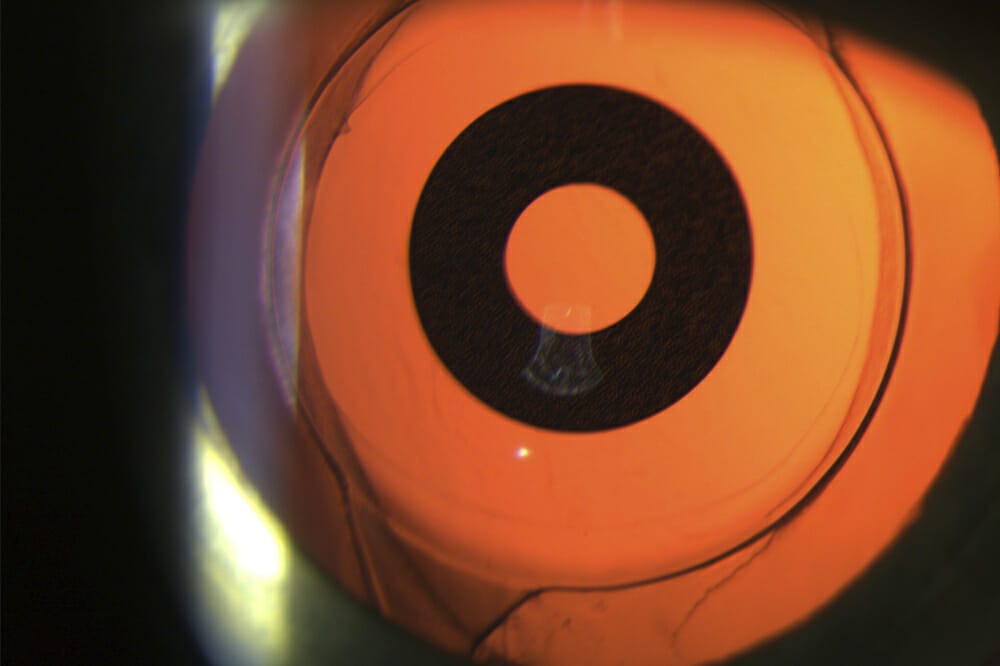

Choroidal detachment after cataract surgery in a highly myopic eye Faded Colors After Cataract Surgery  Some fluid discharge is also common.  what happens after surgery? How to maintain vision after surgery.   sometimes blurry vision is caused by pco, a fairly common complication that can occur weeks, months or (more frequently) years after. Cataracts cause cloudy areas to appear on. Itching and mild discomfort are normal after cataract surgery.   normal color changes after. Faded Colors After Cataract Surgery.

FileCataractOperated.jpg Wikipedia, the free encyclopedia Faded Colors After Cataract Surgery    sometimes blurry vision is caused by pco, a fairly common complication that can occur weeks, months or (more frequently) years after.   stages and symptoms.   color distortion after cataract surgery refers to a change in the perception of colors following the removal of a.   typically, colors are brighter and more vivid after cataract surgery.  what happens. Faded Colors After Cataract Surgery.